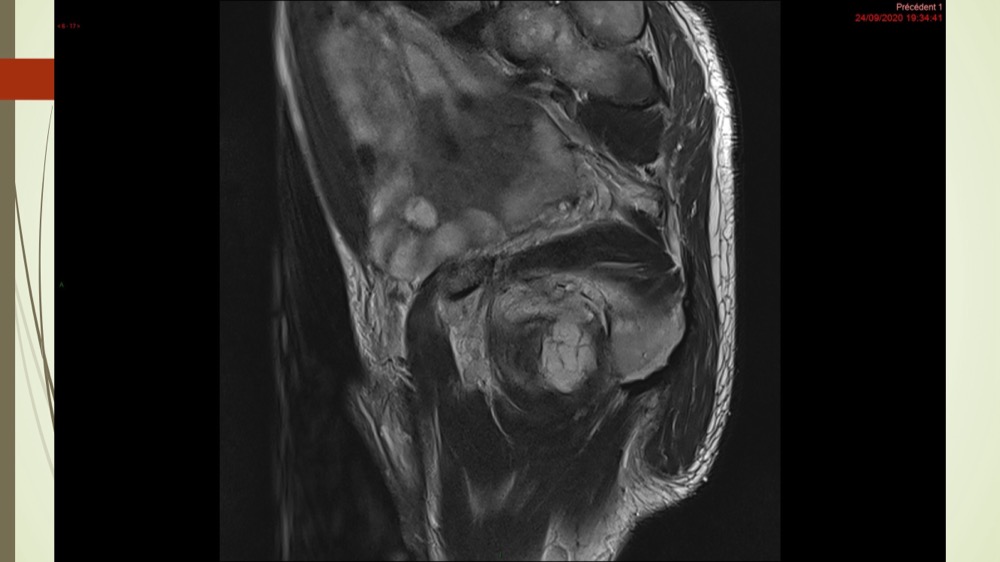

Coxalgie traînante

Kévin Mahé 29/06/2022